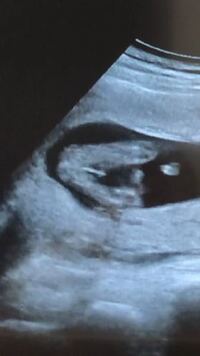

妊娠14週でのエコー画像ですが これは男の子で間違いないでしょうか Yahoo 知恵袋

妊娠16週5日(16w5d)で性別がわかった! 妊娠16週5日(16w5d)のエコー画像 妊娠16週で性別が男の子と確定したエコー画像 PR出産準備が10%オフ!Amazonベビーレジストリに登録しよう! 流産リスクなしの出生前検診って知ってる? 14週で判明!女の子って言われてたのに 14週の時に判明しました。 女の子だとちょっとこの時期にはわかりにくいのではないですかね。 男の子しか産んだことないので、わかりませんが。 上の子の時は7ヶ月くらいまでわからなかったです。10年も前のことなので、その間に心なしかエコー 女の子特有の線が見えたのに確定じゃないの(?_?) エコー写真を見るとうっすら長い何かが見えます。 これは臍の緒でしょうか? 立派な線が3本川の字なので私には女の子に見えるんですが 線が見えてて女の子から男の子に変わった方居ますか?

性別は男の子かなぁ?女の子かなぁ? と、ドキドキしながら妊婦健診に行ってきました。 妊娠15週0日目の2d&4dエコー写真と胎児の大きさ、健診の内容とかかった費用について(今さら)記録しておきます。 妊娠15週0日目の2d&4dエコー写真と胎児の大きさ妊娠14週。いつも通り1030に産婦人科へ。 血圧正常、体重900g増加。 よし。まだプラス1kgもいっていない。 「次からUSB持って来たら 赤ちゃんの映像とってあげられるからね。」 よし。次回は絶対持っていかなきゃ。 エコー始まる。 お。ピコピコ心臓動い 男の子も女の子 も 妊娠30週目の女の子のエコー写真 妊娠後期、30週目の女の子のエコー写真。 足やおしりの部分が分かりづらいのですが、赤い丸のついた部分にコーヒー豆のシンボルがはっきりと映っています。 女の子を見分けるのは足の間の突起物が無いかコーヒー豆が見えるか